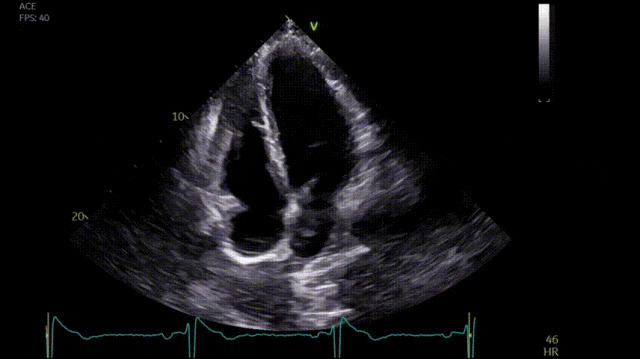

入院时,ECG显示正常窦性心律,心率53次/分,QRS波幅增加,胸前导联ST-T改变显著,表现为ST段抬高和T波倒置,程度超出所谓的“运动员心脏”或早期复极化的解释范围(图2)。系列高敏肌钙蛋白I测量值正常(T0 17 ng/L,T3 52 ng/L,T6 50 ng/L;参考值:男性99百分位数53 ng/L,女性34 ng/L),提示无急性心肌损伤。超声心动图显示左心室(LV)室间隔最大厚度为13 mm,LVEF>55%,心尖部可见一小的瘤样凹陷(视频1)。心脏MRI显示心尖肥厚(11-12 mm),伴有心尖室壁瘤、心部尖晚期钆增强(LGE)和脂肪浸润(图3)。PET未发现心脏炎症。住院3个月后,通道病和心肌病基因突变检测结果均为阴性。

图3. 心脏MRI显示心尖肥厚(11-12 mm),伴有心尖室壁瘤、心尖LGE和脂肪浸润。